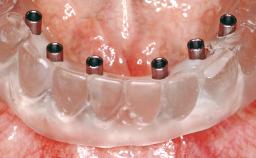

Early Loading of Two Implants in the Mandible and Final Restoration with a Retentive-Anchor-Supported RDP

A 63-year-old male edentulous and maladaptive patient presented with an inability to wear his existing complete maxillary and mandibular dentures. He had been edentulous for 41 years, and there had been three unsuccessful attempts by dentists to provide complete dentures for him. Efforts to wear both complete dentures were always initially encouraging, but over time, he invariably found that he was unable to wear the complete mandibular denture, and this pattern had persisted for 20 years. After seeing local newspaper advertisements, he requested having his complete mandibular denture stabilized with implants.

# of Implants 2

Type of Implants One-Piece

Modality 2 interforaminal implants